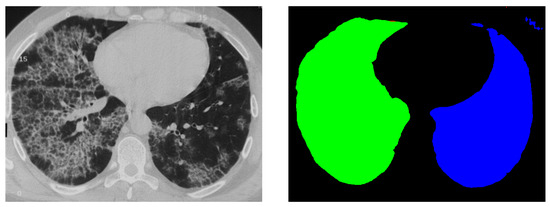

The LUNA16 (Lung Nodule Analysis 2016) dataset [14] was used for training and evaluating our model. This publicly available dataset is a subset of the larger LIDC-IDRI database and contains 888 thoracic CT scans with accompanying annotations for lung nodules. The scans are provided in the MetaImage format (.mhd/.raw) and have a typical resolution of 512 × 512 pixels per slice (Figure 1), with varying slice thicknesses ranging from 0.6 to 3 mm.

Figure 1.

Overview of 2D image slices in LUNA16: original 2D image (top); original segmentation label (bottom).